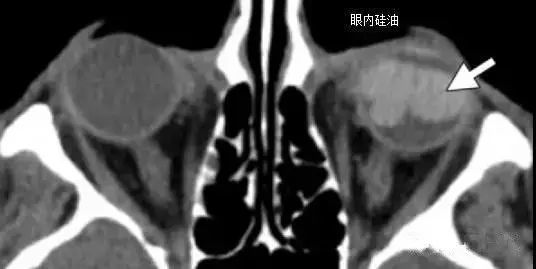

3.常见的用于治疗视网膜脱离的材料包括巩膜条带 , 硅油 , 以及气体 。

文章插图